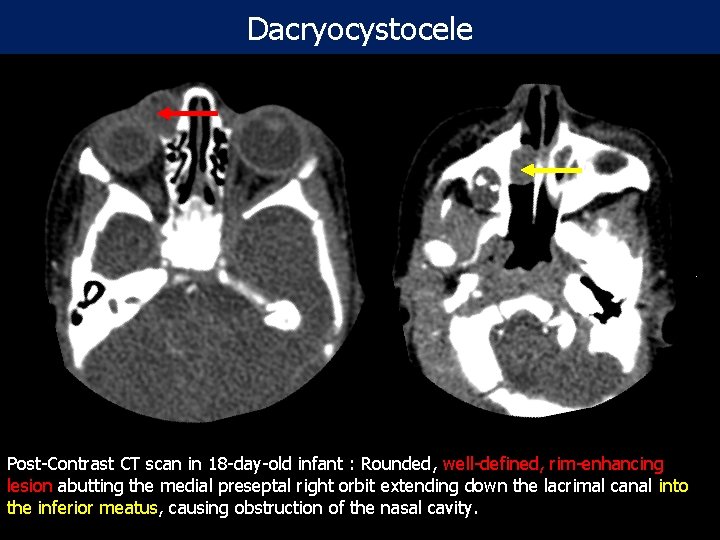

Dacryocystocele Post-Contrast CT scan in 18 -day-old infant : Rounded, well-defined, rim-enhancing lesion abutting the medial preseptal right orbit extending down the lacrimal canal into the inferior meatus, causing obstruction of the nasal cavity.